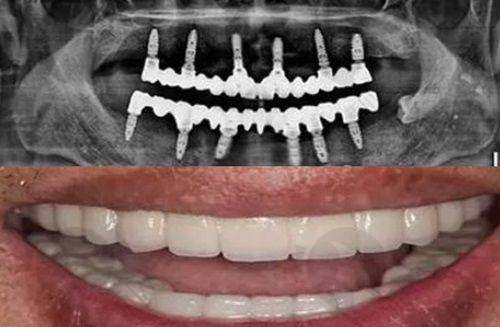

在种植牙领域,牟家云医生擅长即刻种植、智能化导航种植,手术风格细腻稳健;刘国辉、杨朝晖等医生在高难度种植(如All - on - 4、穿颧穿翼种植)方面经验多。祖元章从业至今经手近万颗种植牙修复工作,对于微创种植、上颌窦提升术、半口全口种植等种植手术有着丰富经验。黄涛擅长部分牙列缺损,擅长普通种植、即刻种植、微创种植牙、微创即刻种植。

医院还引进了大量海内外精良的口腔诊疗设备。3D影像口腔CBCT系统能360度扫描口腔结构,精密定位牙槽骨、神经管等关键部位,为种植牙、正畸等手术提供精细数据支持。数字化种植导航系统通过计算机模拟种植路径,医生可以像“开导航”一样精细操作,减少手术创伤和误差。根管显微镜、超声骨刀让牙髓治疗、拔牙等操作更精细,患者体验更舒适。医用包装封口机、数字化高压灭菌器严格遵循消毒流程,避免交叉感染。